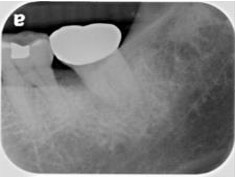

術後一年之全口X光片, #37近心側可見明顯骨充填與放射線密度增加。 牙周再生手術完成一年後追蹤,全口牙齦發炎狀況改善,牙周組織呈現健康狀況。#37金屬燒附陶瓷牙冠製作完成。